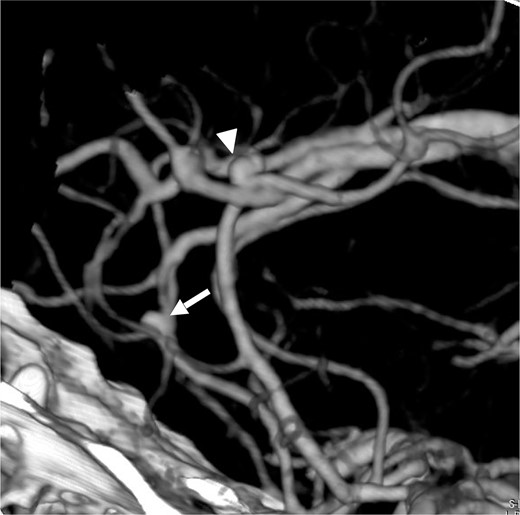

A man in his fifties presented with sudden severe headache that showed no improvement. Initial CT at another hospital revealed SDH, prompting referral to our institution. Head CT demonstrated left SDH including the interhemispheric fissure (Fig. 1). 3D-CTA performed at the referring hospital revealed ⁓5-mm saccular aneurysms at the left ICA and right basilar-superior cerebellar artery junctions, along with left A3-A4, and right A2-A3 aneurysms (Fig. 2). Preoperative FLAIR imaging showed no evidence of SAH (Fig. 3). As the initial 3D-CTA inadequately captured the distal portions of the ACA, we performed repeat imaging upon admission, which revealed an additional left A3A4 DACA aneurysm. However, due to the DACA aneurysm being smaller than the ICA aneurysm, definitive determination of the rupture source was not possible.

Lateral view (left to right) of three dimensional CT angiography taken at our clinic, showing cerebral aneurysm in the ACA of right A2A3 (white arrow) and left A3A4 (white arrow head).